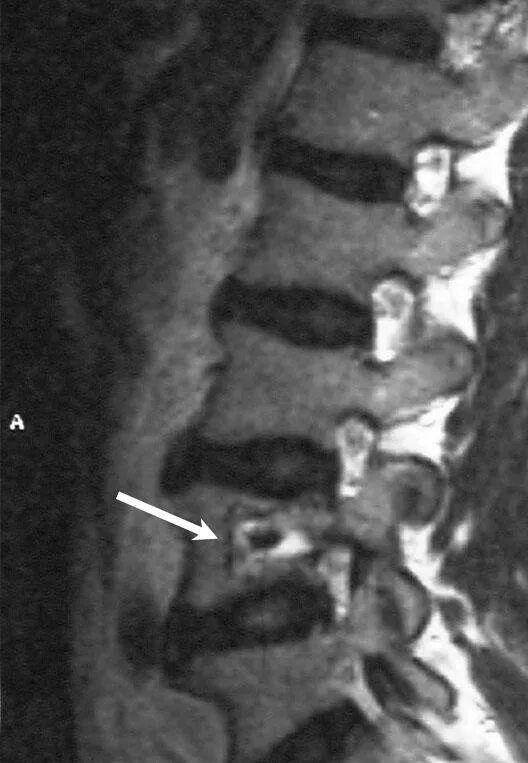

Остеома мрт